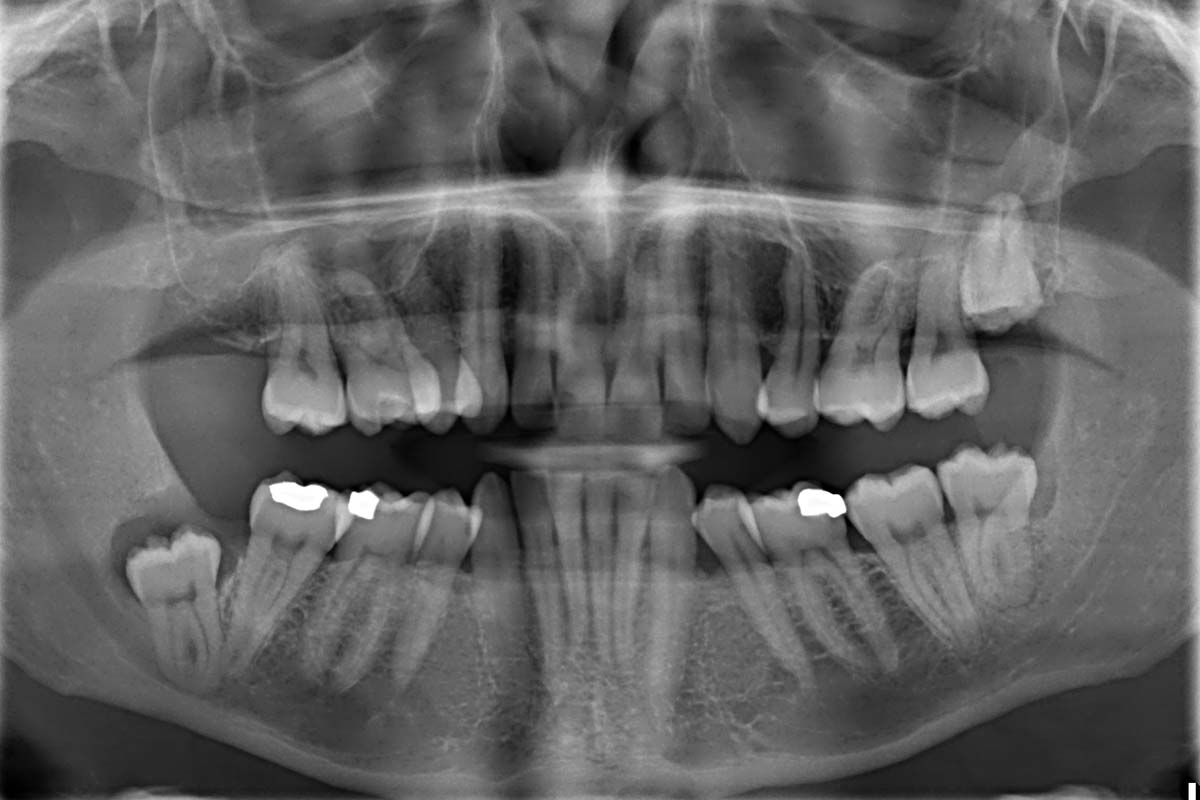

How Safe Are Dental X Rays at Sam Monier blog